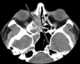

Enlarged orbital rectus muscles

Extraorbital extracranial lesion extending to the orbit

Eyeball deformity